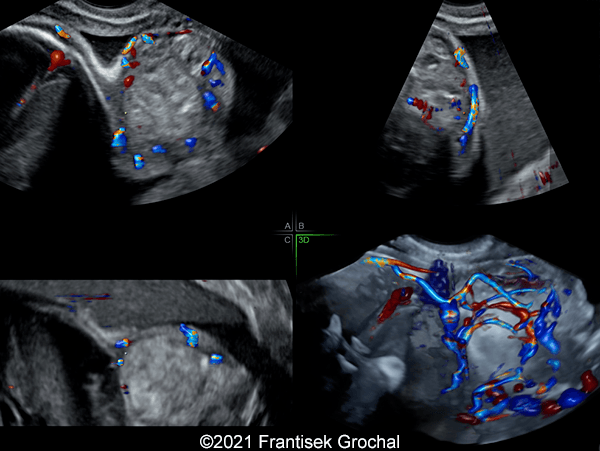

Case Report: A 24-year-old secundigravida, primipara presented to our office at 24 weeks and 6 days of her pregnancy due to a right-sided cranial parieto-occipital mass of the fetus. We obtained the following images.

Our ultrasound images at 24 weeks, 6 days show a highly vascularized, mostly solid mass measuring 58 x 45 x 34mm in the right-parieto-occipital subcutaneous region. Vascular supply of the lesion could be traced to the right vertebral artery. Repeat ultrasound exams done later in pregnancy demonstrated that the size of the mass remained stable with overall mass volume about 58 cm³.